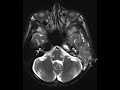

Petrous Apex Abscess

These images demonstrate complete opacification of the left mastoid air cells with peripheral air cell enhancement and restricted diffusion in the petrous apex compatible with abscess. There may be smaller abscesses in the posterior mastoid air cells. The coronal MRV MIP image shows thrombosis of the distal left sigmoid venous sinus and internal jugular vein, a well known complication of acute otomastoiditis. No subperiosteal abscess or extracranial abscess was present.